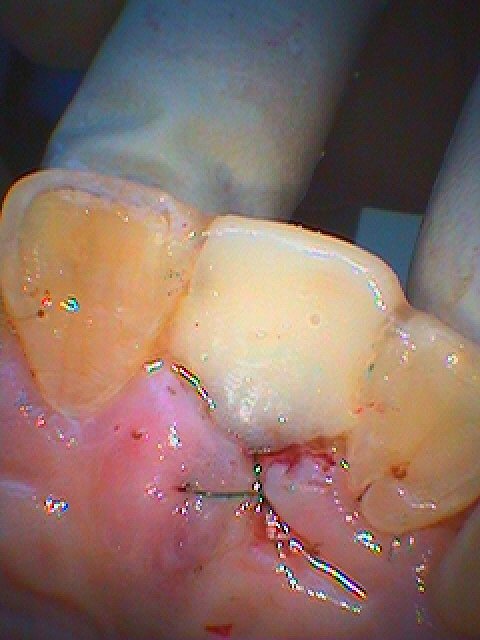

歯茎が下がるのではなく上がってきているのが審美的にも

綺麗に仕上がるカギといえます

ジルコニアカスタムアバットメントを建てていきました